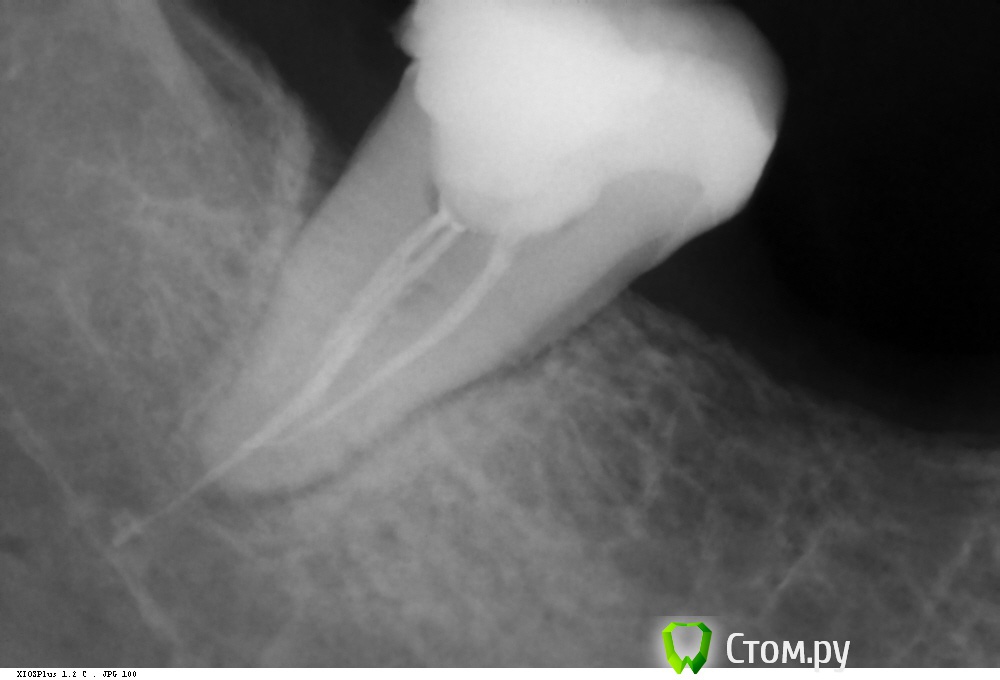

kaplia77 Опубликовано 5 ноября, 2014 Поделиться Опубликовано 5 ноября, 2014 Здравствуйте! Очень нуждаюсь в ваших советах! Ситуация следующая. Неделю назад была депульпирована нижная семерка справа( кажется правильно называется 47 зуб). После отхождения заморозки зуб ныл. Через сутки сильно заболел зуб и пол челюсти справа, и одновременно онемел подбородок, нижняя губа и десна. Врач сказала, что это нормально и все пройдет. Я пошла на консультацию к другому врачу,так как боль еще усилилась. Был сделан снимок. на котором видно, что гуттаперча вышла за пределы канала. Вскрыли каналы. В одном обнаружилась живая пульпа. Снова все зачистили и положили временную пломбу. Через канал гуттаперчу удалить не удалось. Через 2 дня болит уже не так сильно. Но онемение так и осталось. Собственно вопрос в том , нужно ли удалять зуб и гуттаперчу? Врач считает, что не нужно. Так как на чувствительность это не повлияет. Нерв постепенно восстановится. Снимок прилагаю. Ссылка на комментарий

kaplia77 Опубликовано 5 ноября, 2014 Автор Поделиться Опубликовано 5 ноября, 2014 вот такой снимок последний. после него положили лекарство и временную пломбу. Ссылка на комментарий

Гарриевич Опубликовано 5 ноября, 2014 Поделиться Опубликовано 5 ноября, 2014 по моему мнению, онемение связано с материалом за пределами корня зуба, который создает компрессию нижнечелюстного нерва. не будет материала, не будет и онемения Ссылка на комментарий

SDC Опубликовано 5 ноября, 2014 Поделиться Опубликовано 5 ноября, 2014 Т.е. мне надо сделать еще один снимок и 3д томографию, правильно?Сначала только прицельный снимок после завершения лечения корневых каналов и название материалов для пломбировки в 1 и во 2 случае. Обратите внимание Вашего Доктора, что Ваш зуб имеет систему к.к. С-шейп. Требуется тщательнейшая ультразвуковая обработка каналов и/или применение SAF https://www.google.ru/search?client=opera&q=САФ+для+обработки+каналаов&sourceid=opera&ie=UTF-8&oe=UTF-8#newwindow=1&q=SAF+%D0%B4%D0%BB%D1%8F+%D0%BE%D0%B1%D1%80%D0%B0%D0%B1%D0%BE%D1%82%D0%BA%D0%B8+%D0%BA%D0%B0%D0%BD%D0%B0%D0%BB%D0%BE%D0%B2 Ссылка на комментарий

SDC Опубликовано 5 ноября, 2014 Поделиться Опубликовано 5 ноября, 2014 (изменено) Необзодимо сделать КТ этого участка (или полностью все полости рта, как угодно), чтобы оценит расположение материала за верхушкой, относительно нижнечелюстного нерваГарриевич, а что это нам даст в плане рекомендаций?Как бы ни был расположен вышедший силер/филер относительно н.ч. канала, мы ничего, кроме удаления этого силера, предложить не сможем.Удаление зуба, в любом случае, не приведет к удалению излишков материала за апексом.Ревизия через лунку удаленного зуба осложена плохой визуализацией.Удаление силера наружным доступом в обл. 2М травматично. Вся надежда на то, что парестезия развилась из-за периапикального воспалительного процесса (область периапикальной радиолюцентности слегка просматривается на прицельном снимке)Для более-менее объективного прогноза продолжительности парестезии, в противном случае, необходимо знать состав силера. Изменено 5 ноября, 2014 пользователем SDC Ссылка на комментарий

Гарриевич Опубликовано 6 ноября, 2014 Поделиться Опубликовано 6 ноября, 2014 Я думаю могла быть прямая травма инструментом при овере, а не просто силером, + это может быть не излишк силера, а целая гуттаперча, которая оттула никуда не денется. пока не запломбировали, можно постараться ее оттуда вытащить. В свете всего этого КИ считаю не лишним Ссылка на комментарий